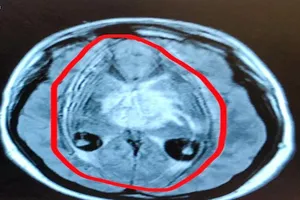

Khối u não hiếm hình thành từ… tế bào tinh trùng